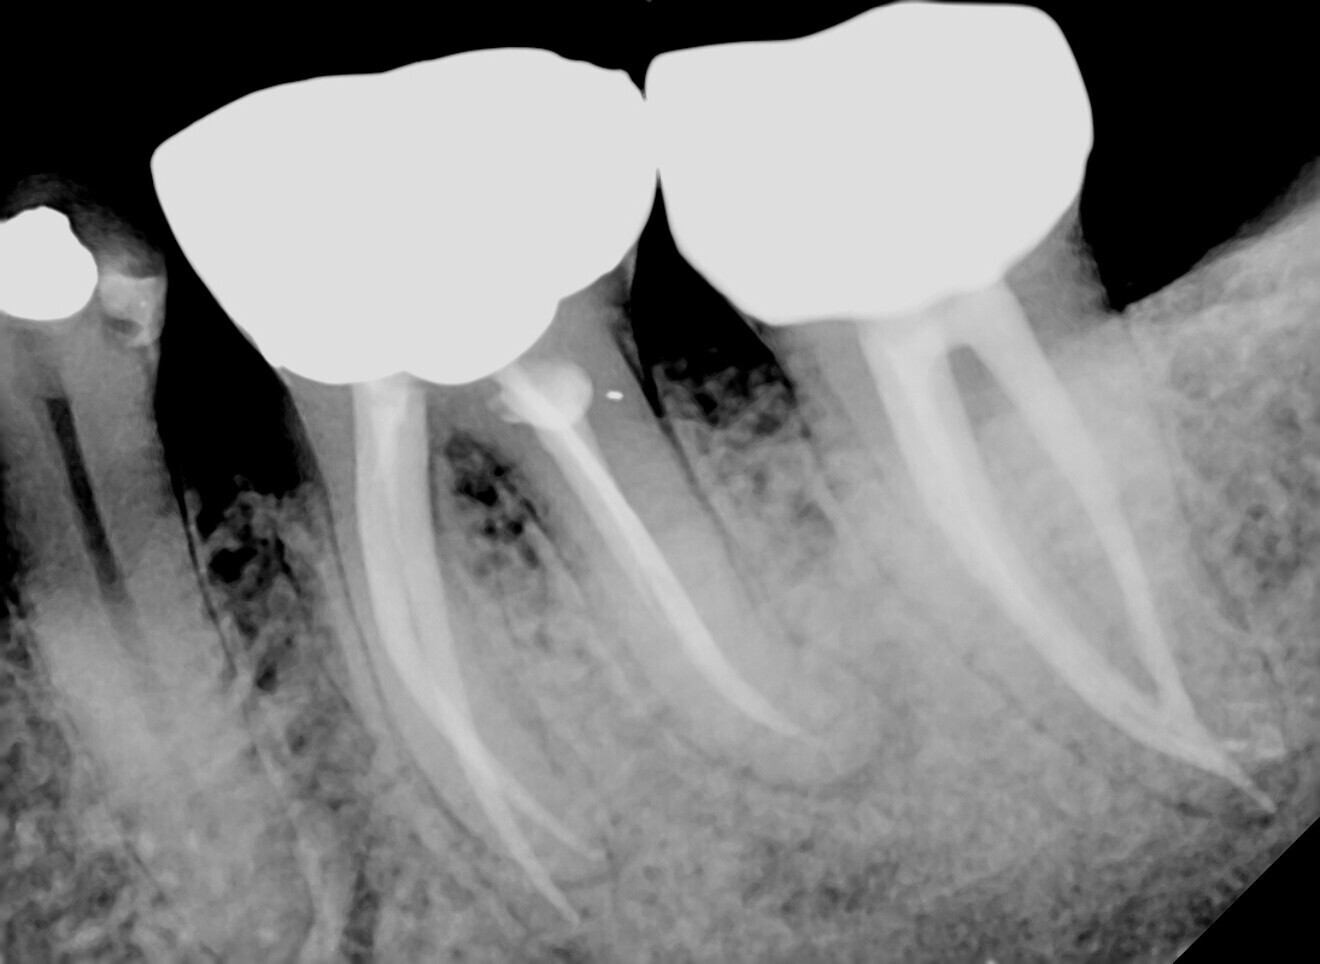

A 72-year-old patient presented to our clinic for whom crown treatment of tooth #37 was planned owing to the patient complaining of recent pain on biting without lingering symptoms. However, the procedure was delayed owing to COVID-19 lockdown orders, and when the patient returned for treatment, he reported that symptoms had escalated to constant aching during the day and night, subsiding after a week. On examination, tooth #37 was tender to percussion and not responsive to cold testing and showed an associated periapical radiolucency on the radiograph (Fig. 1).

Fig. 1. (All images: Dr Brenda Loh)

The patient’s heavy bruxing habits had led to the formation of fractures in the enamel and dentine. Further propagation of the fractures had led to pulpal irritation and bacterial ingress, which caused irreversible pulpitis and ultimately pulp death. The diagnosis was pulp necrosis and symptomatic periapical periodontitis.